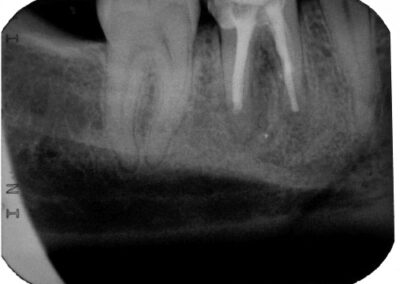

Fall 1:

Unmittelbar nach WF nach Desinfektion nach dem Timbuktu-Protokoll im Januar 2008 bei klinischer Beschwerdefreiheit (Klick!)